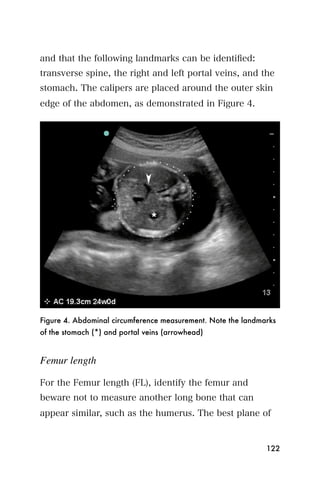

center that is the endometrium.

Figure 3. The bladder (*) and empty uterus (arrow)

An empty uterus may cause the clinician to worry about

an ectopic pregnancy. A ruptured ectopic pregnancy

blood may extend into the abdomen, so it is important

107

to look for blood within the abdomen as well as the

pelvis. The sonographer can begin imaging the area

between the liver and the kidney on the mother s right

side. This is the same window that is used to look for

blood in the trauma exam (Figure 4).

Figure 4. Blood (arrowheads) between the liver (*) and kidney. The